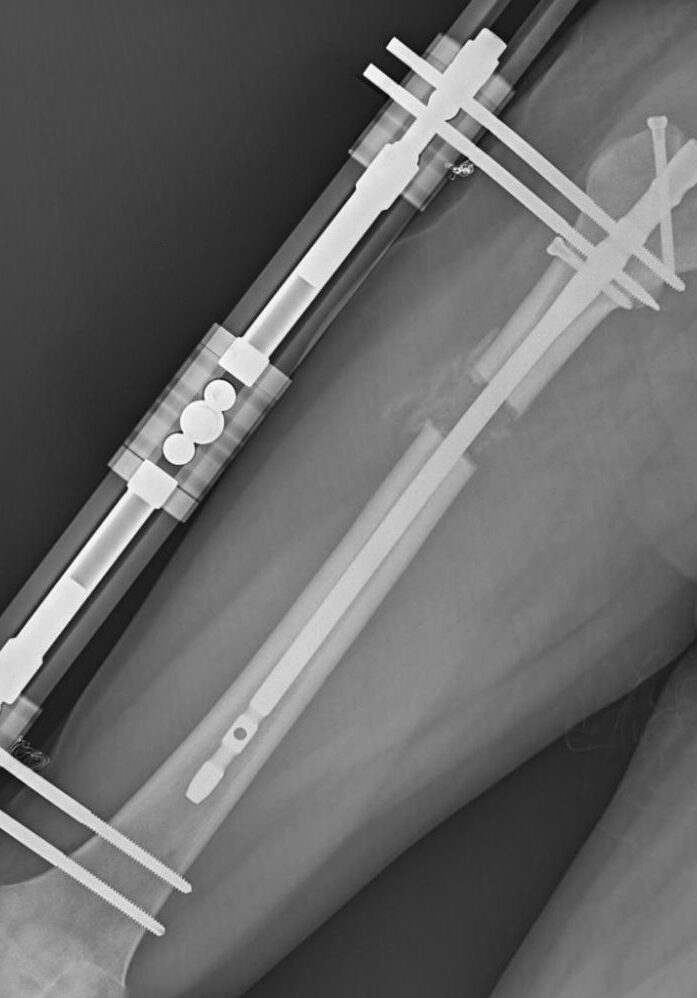

MÉTODO LON

Sistema Combinado: Interno y Externo

Combina un clavo intramedular con un fijador externo temporal. Es el método con mayor capacidad de alargamiento y el mejor equilibrio entre costo, seguridad y resultados.

El fijador externo se usa durante la fase de alargamiento (2-3 meses)